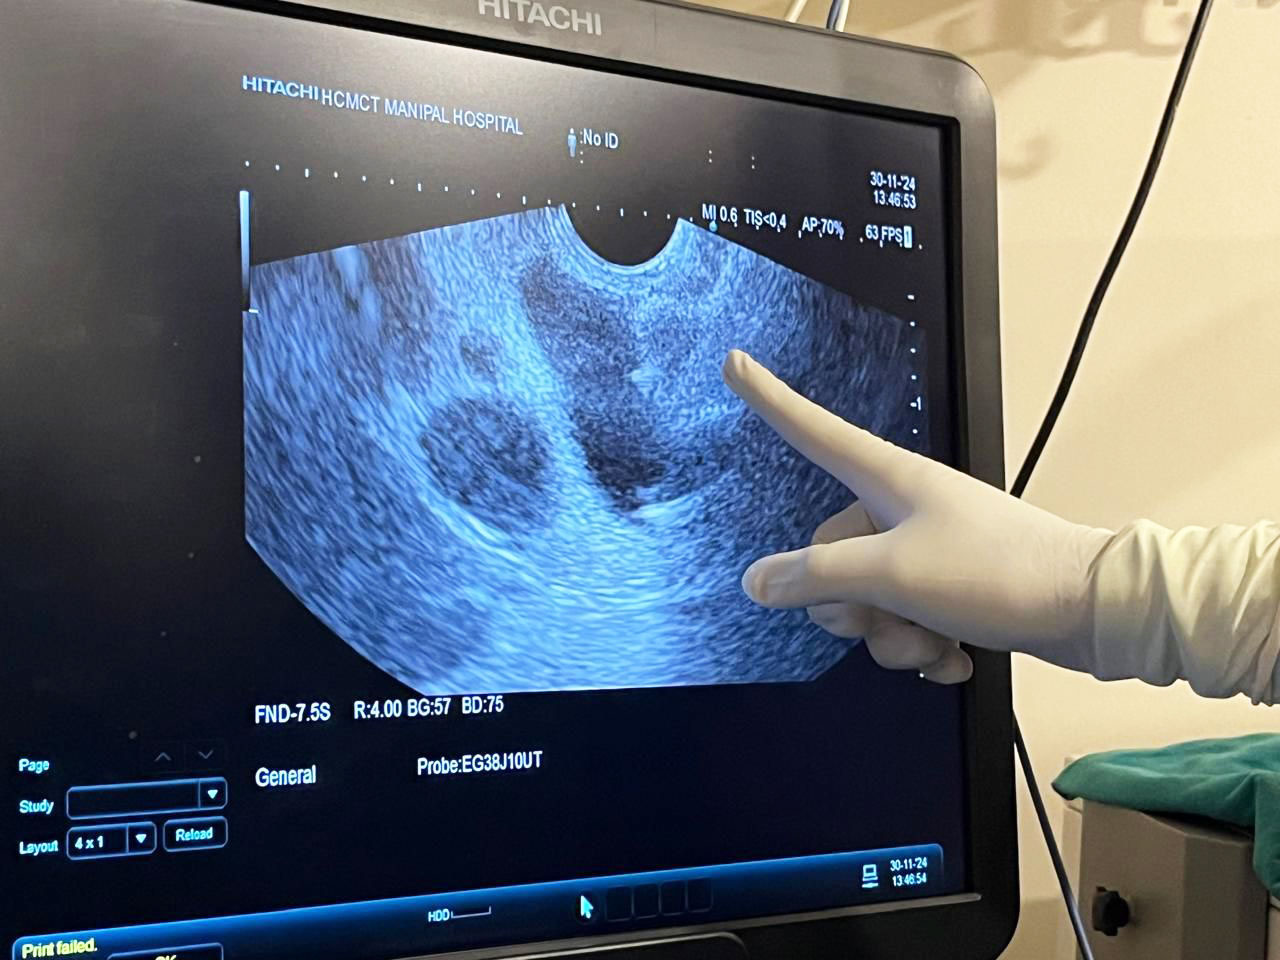

Happy to share a first for us at Manipal Hospital Delhi on 30th November: Endoscopic Ultrasound (EUS) guided Choledocho-Duodenostomy for relief of malignant biliary obstruction. Mr SL, 68 years, was hospitalized with us for obstructive jaundice and cholangitis. Evaluation revealed growth in head of pancreas with liver mets. EUS Guided FNA with ROSE ( Rapid Onsite Evaluation) by pathologist confirmed Adenocarcinoma pancreas. At ERCP the guide-wire could not be negotiated proximal to the growth in pancreas. Such patients with failed ERCP are normally referred worldwide for PTBD(percutaneous trans-hepatic biliary drainage). We decided, instead, to access the bile duct, proximal to the obstruction, from the duodenum(D1) and with EUS guidance, place a Lumen Apposing Metal Stent(LAMS), thus establishing biliary drainage into duodenum. Procedure time was under 15 minutes and the patient is doing well.

The proximal end of the stent in dilated bile duct